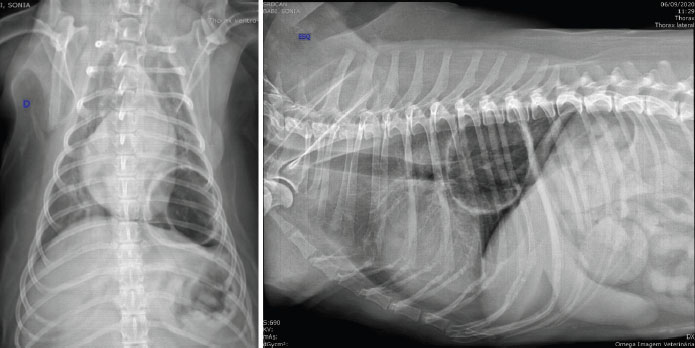

Even though the cardiac silhouette looked normal in the radiography, the dog was diagnosed with moderate mitral insufficiency by echocardiography. The patient was referred to a tomographic examination of the thoracic cavity. The CT images were acquired with a 1-row detector helical CT unit (Somatom Spirit, Siemens; 1,5 pitch, 1s rotation time, 130 de Kv and 70 de mAs). We observed thickening of the bronchial walls and an extensive structure, filled with air, oval to round in shape, with hyperattenuated, thick and irregular walls, approximately 0.4 cm thick (Fig. 2). The CT after intravenous contrast has not been performed, because the owner did not allow it, so the solid part of the tumor could not be contrasted. The structure was located in the perihilar region of the left caudal lung lobe, and it was in contact with its bronchial branches and air bronchogram. It measured approximately 6.6 × 4.5 × 5.9 cm; compatible with aberrant bronchiectasis or a low-grade pneumatocele (Fig. 2). This structure created a medial displacement and luminal compression of the main bronchus of the left caudal pulmonary lobe. In the bifurcation of this main bronchus, its branches moved medially and followed the medioventral and mediodorsal walls of the bullae, respectively, with the ventral branch slipping into the lumen of the bullae. We did not observe lymphomegalies.

Fig. 2. Tomographic images in axial (left) and dorsal (right) views, in which we observe the thickening of the bronchial walls. Moreover, we can observe a structure filled with air, of round shape, with hyperattenuated, thick and irregular walls. It is located in the perihilar region of the left caudal pulmonary lobe in contact with bronchial branches and air bronchograms.